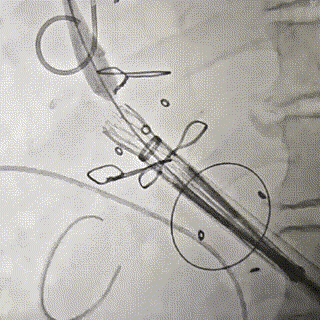

泥鳅导丝配合多功能导管跨二尖瓣,置入加硬导丝建立通路

瓣膜释放,位置良好

主动根部造影,冠脉显影良好,无漏

回收输送系统,撤出体外,无需造影,收紧荷包